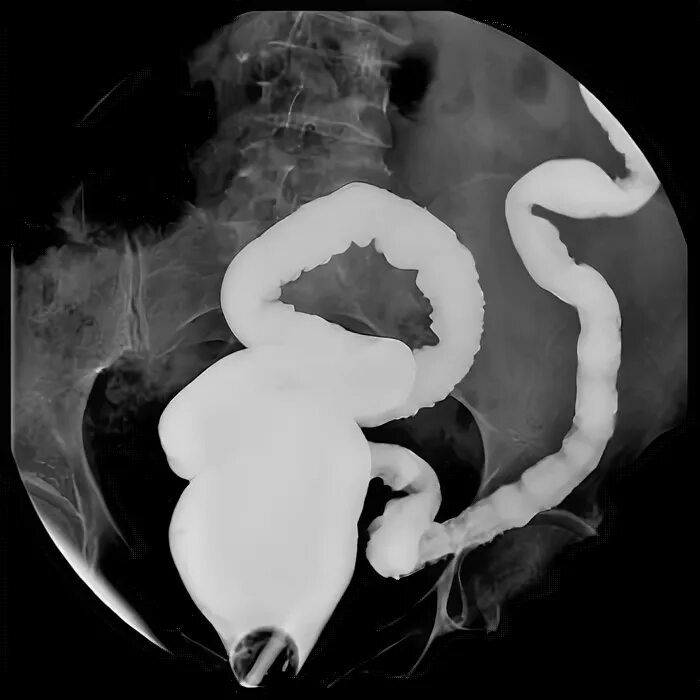

Узи прямой кишки как делают